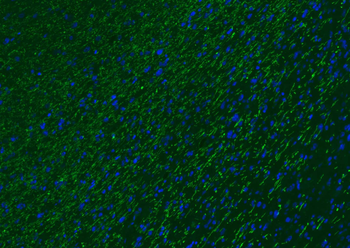

Paraformaldehyde-fixed, paraffin embedded (human brain), Antigen retrieval by boiling in sodium citrate buffer (pH6.0) for 15 min, Blocking buffer (normal goat serum) at 37°C for 30 min, Antibody incubation with (MBP) Polyclonal Antibody, Unconjugated (orb783422) at 1:200 overnight at 4°C, followed by a conjugated Goat Anti-Rabbit IgG antibody for 90 minutes, and DAPI for nuclei staining.